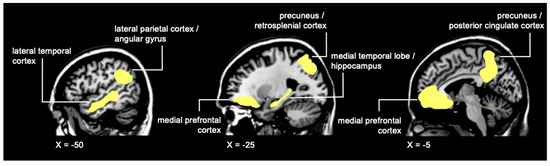

- Buckner, R.L.; Andrews-Hanna, J.R.; Schacter, D.L. The Brain’s Default Network: Anatomy, Function, and Relevance to Disease. Ann. N. Y. Acad. Sci. 2008, 1124, 1–38. [Google Scholar] [CrossRef]

- Spreng, R.N.; Mar, R.A.; Kim, A.S.N. The Common Neural Basis of Autobiographical Memory, Prospection, Navigation, Theory of Mind, and the Default Mode: A Quantitative Meta-Analysis. J. Cogn. Neurosci. 2009, 21, 489–510. [Google Scholar] [CrossRef]

- Andrews-Hanna, J.R.; Reidler, J.S.; Sepulcre, J.; Poulin, R.; Buckner, R.L. Functional-Anatomic Fractionation of the Brain’s Default Network. Neuron 2010, 65, 550–562. [Google Scholar] [CrossRef] [PubMed]

- Spreng, R.N.; Grady, C.L. Patterns of Brain Activity Supporting Autobiographical Memory, Prospection, and Theory of Mind, and Their Relationship to the Default Mode Network. J. Cogn. Neurosci. 2010, 22, 1112–1123. [Google Scholar] [CrossRef] [PubMed]